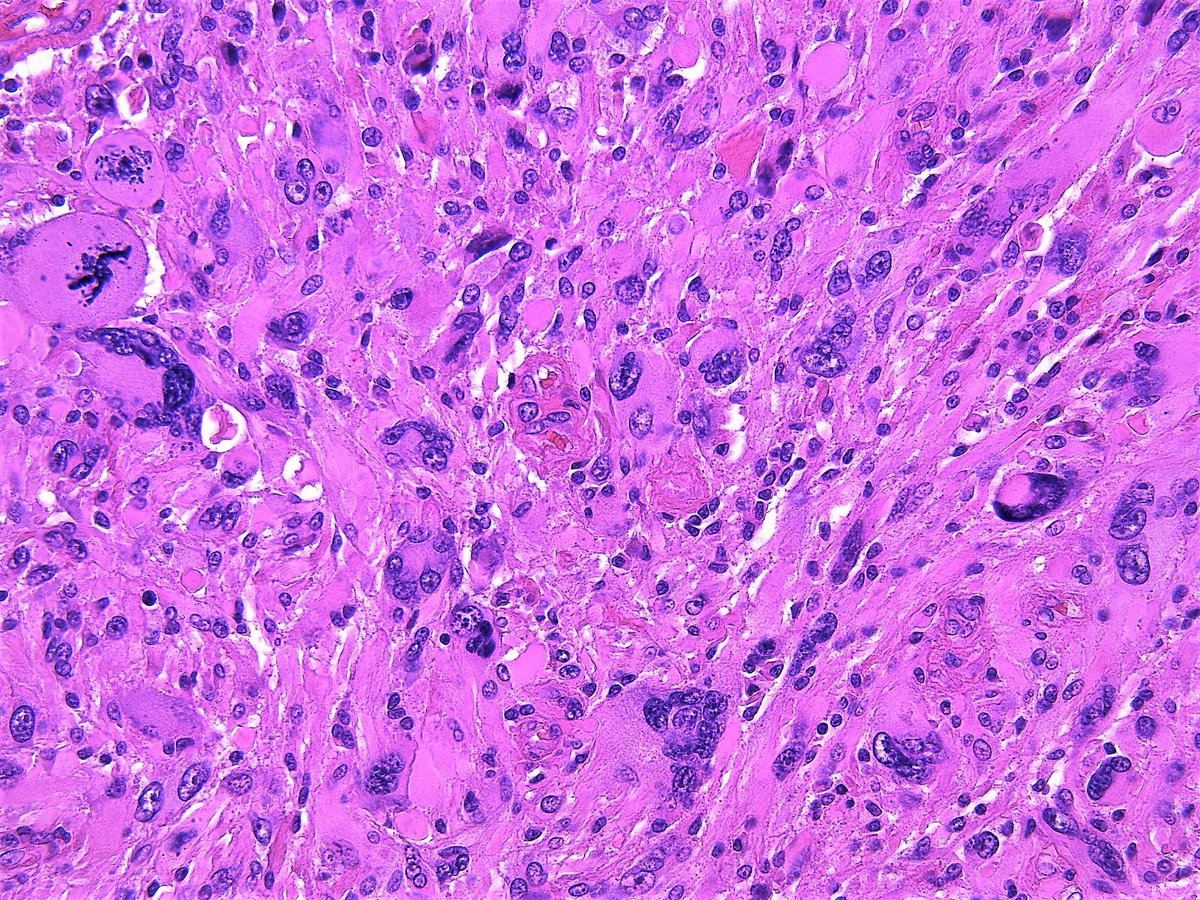

Pathology WalkerAuto Tweet Bot on Twitter "Giant cell glioblastoma Death Rattle Glioblastoma sometimes in the last few hours, there can be a sort of rattle to their breathing. The death rattle refers to the noisy breathing caused by the. glioblastoma is the most common type of primary brain tumor in adults and is nearly universally fatal despite advances in therapy. This can be a bit alarming and some people find. Death Rattle Glioblastoma.

Pathology WalkerAuto Tweet Bot on Twitter "Giant cell glioblastoma Death Rattle Glioblastoma death rattle is a sign that death may occur in hours or days. Rattle can be very upsetting for those at the bedside. The death rattle refers to the noisy breathing caused by the. in most cases, the process leading to death is not sudden for patients with glioblastoma. we’ve compiled a list of the signs and. Death Rattle Glioblastoma.